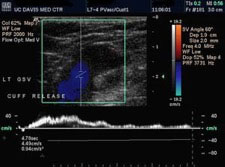

In the lower extremities, blood returns to the heart through a network of deep and superficial veins. Standard venous flow patterns depend on open venous channels and the function of numerous valves within the veins. Venous insufficiency may occur if veins are obstructed from a chronic thrombus (blood clot), for example, or if the valves are incompetent — no longer providing for only one-way flow. Venous valvular incompetence in superficial veins or communicating veins (veins that connect the deep and superficial veins) can result in varicose veins. Untreated chronic venous insufficiency in the deep or superficial venous system can cause progressive symptoms that include: pain, swelling, skin changes, and eventual tissue breakdown ( Ulcers).

Ultrasound scanning of the deep and superficial veins can be utilized to detect obstruction. Ultrasound also is used to evaluate the function of valves in each segment of the evaluated veins. Using Ultrasound(duplex scanning) the direction of blood flow can be evaluated. The examination is often done in the upright position, as this is the best way to evaluate valve function.

Evaluation of the function of the lower extremity veins is not needed in every case, but when surgical treatment, sclerotherapy, or saphenous venous ablation (closure) is being considered, a complete lower-extremity venous duplex scan can provide valuable information that may guide therapy. A comprehensive study may include both lower extremities.

No special preparation is required. A complete study usually takes about 30 to 60 minutes.

Treatment of venous insufficiency always includes the three “E’s” elevation of the leg, exercise, and use of elastic compression. In cases where intervention or surgery is considered, the duplex scan can provide essential information about which vein segments are abnormal, whether obstruction or reflux is present (or both), and how extensive a problem exists. This information will guide the vascular specialist’s recommendations and provide information that may help predict how successful treatment might be.